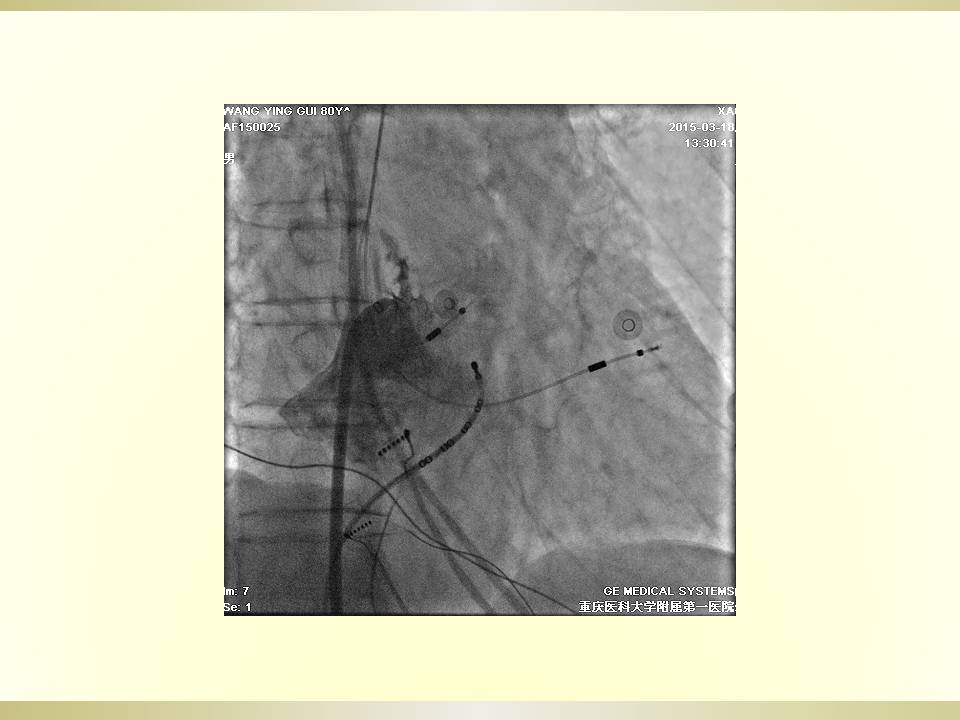

房速1例的射频消融

雷森 何泉